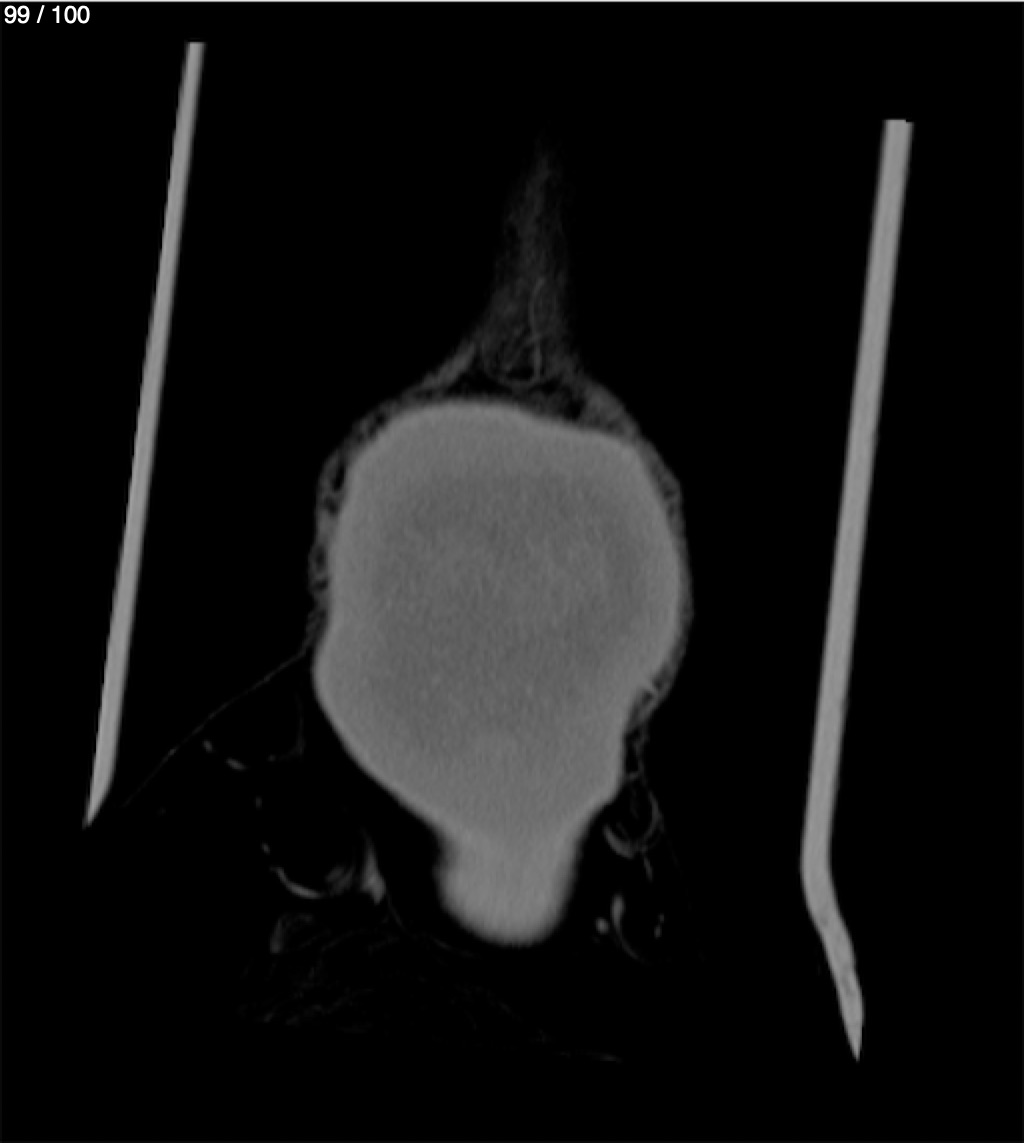

Reybet Garcia Fuentes 30A - T.C Craneo